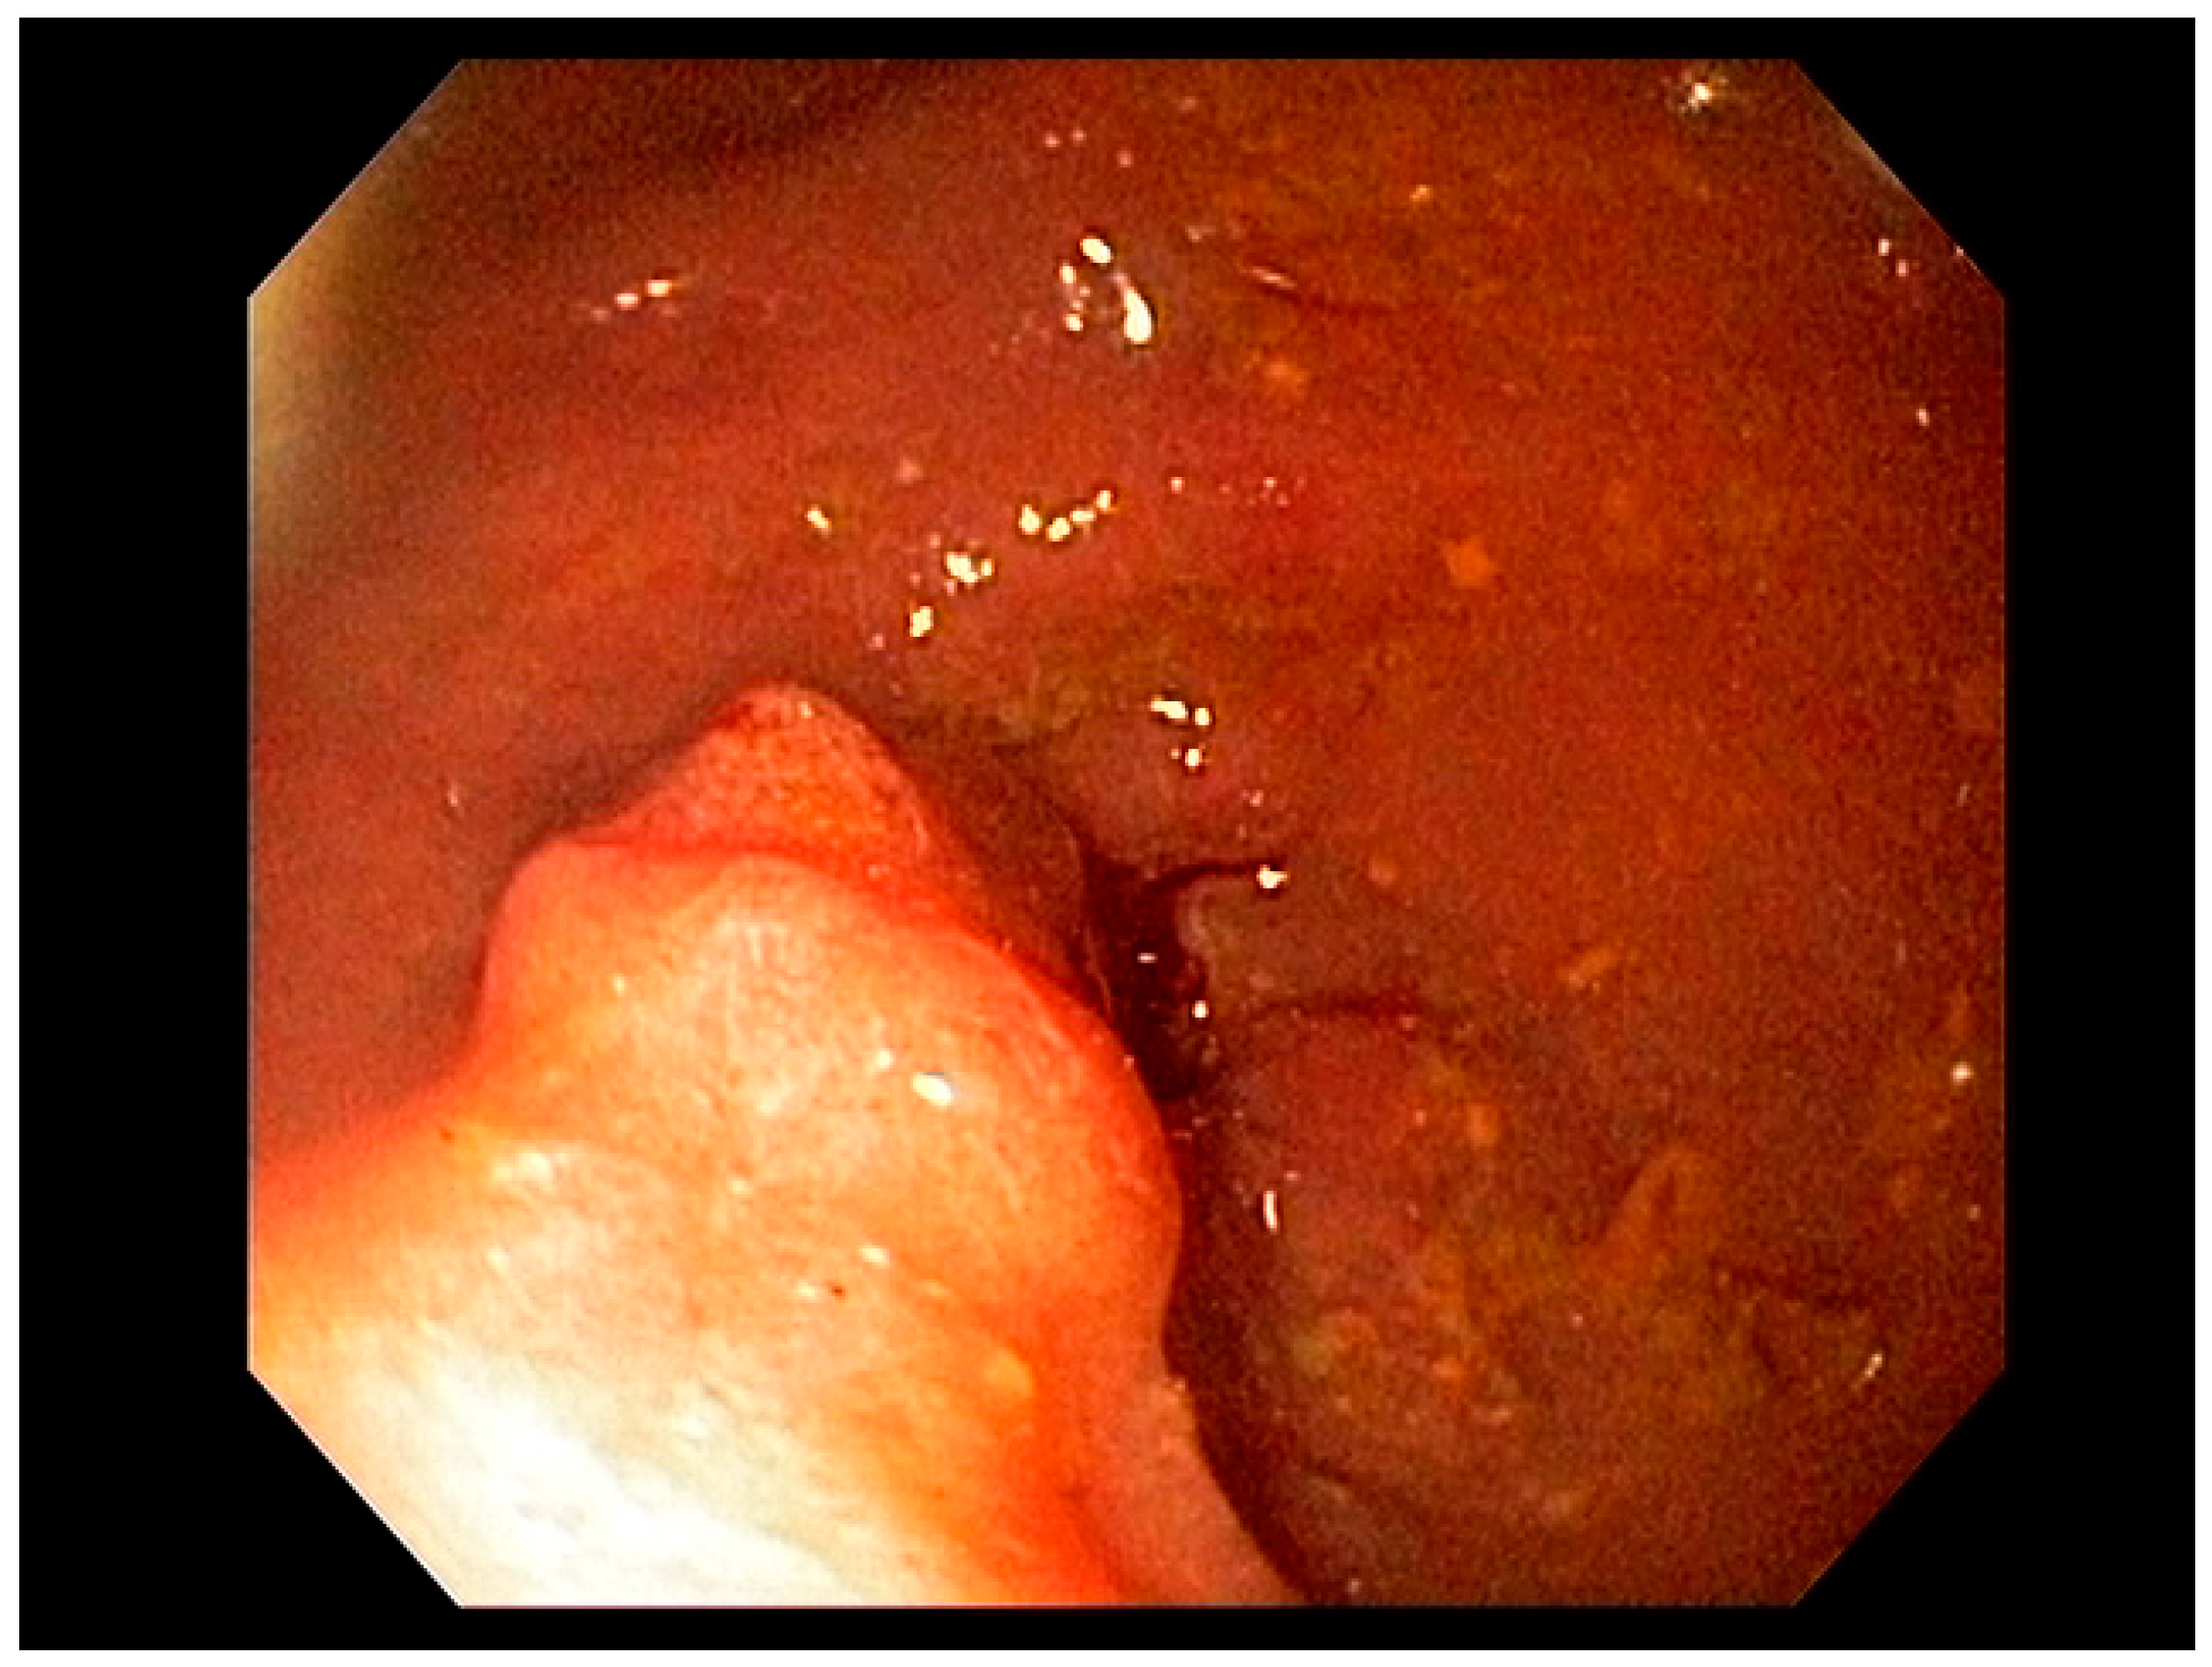

4.3. Endoscopic Ultrasound in Staging of Gastric Cancer

- Spolverato, G.; Ejaz, A.; Kim, Y.; Squires, M.H.; Poultsides, G.A.; Fields, R.C.; Schmidt, C.; Weber, S.M.; Votanopoulos, K.; Maithel, S.K.; et al. Use of Endoscopic Ultrasound in the Preoperative Staging of Gastric Cancer: A Multi-Institutional Study of the US Gastric Cancer Collaborative. J. Am. Coll. Surg. 2015, 220, 48–56. [Google Scholar] [CrossRef] [PubMed]

- Mocellin, S.; Pasquali, S. Diagnostic accuracy of endoscopic ultrasonography (EUS) for the preoperative locoregional staging of primary gastric cancer. Cochrane Database Syst. Rev. 2015, 2015, CD009944. [Google Scholar] [CrossRef]

- Redondo-Cerezo, E.; Martínez-Cara, J.G.; Jiménez-Rosales, R.; Valverde-López, F.; Caballero-Mateos, A.; Jérvez-Puente, P.; Ariza-Fernández, J.L.; Úbeda-Muñoz, M.; López-De-Hierro, M.; De Teresa, J. Endoscopic ultrasound in gastric cancer staging before and after neoadjuvant chemotherapy. A comparison with PET-CT in a clinical series. United Eur. Gastroenterol. J. 2017, 5, 641–647. [Google Scholar] [CrossRef]